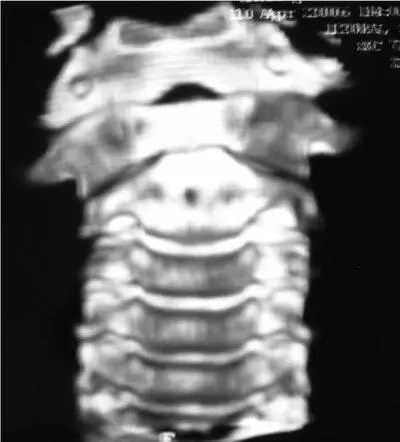

Рис. 6.12.КТ-контроль после 5 недель вытяжения. Практически правильное положение атланта

Деротационное Halo вытяжение производилось в течение 5 недель. Удалось вывести голову в правильное положение. На КТ контроле произошло неполное вправление атланта с сохранением смещение до 2,5 мм правого атланто-аксиального сустава кпереди (рис. 6.12).

Рис. 6.13.КТ-контроль через 1 год. Положение атланта горизонтальное. Синостоз правого атланто-аксиального сустава